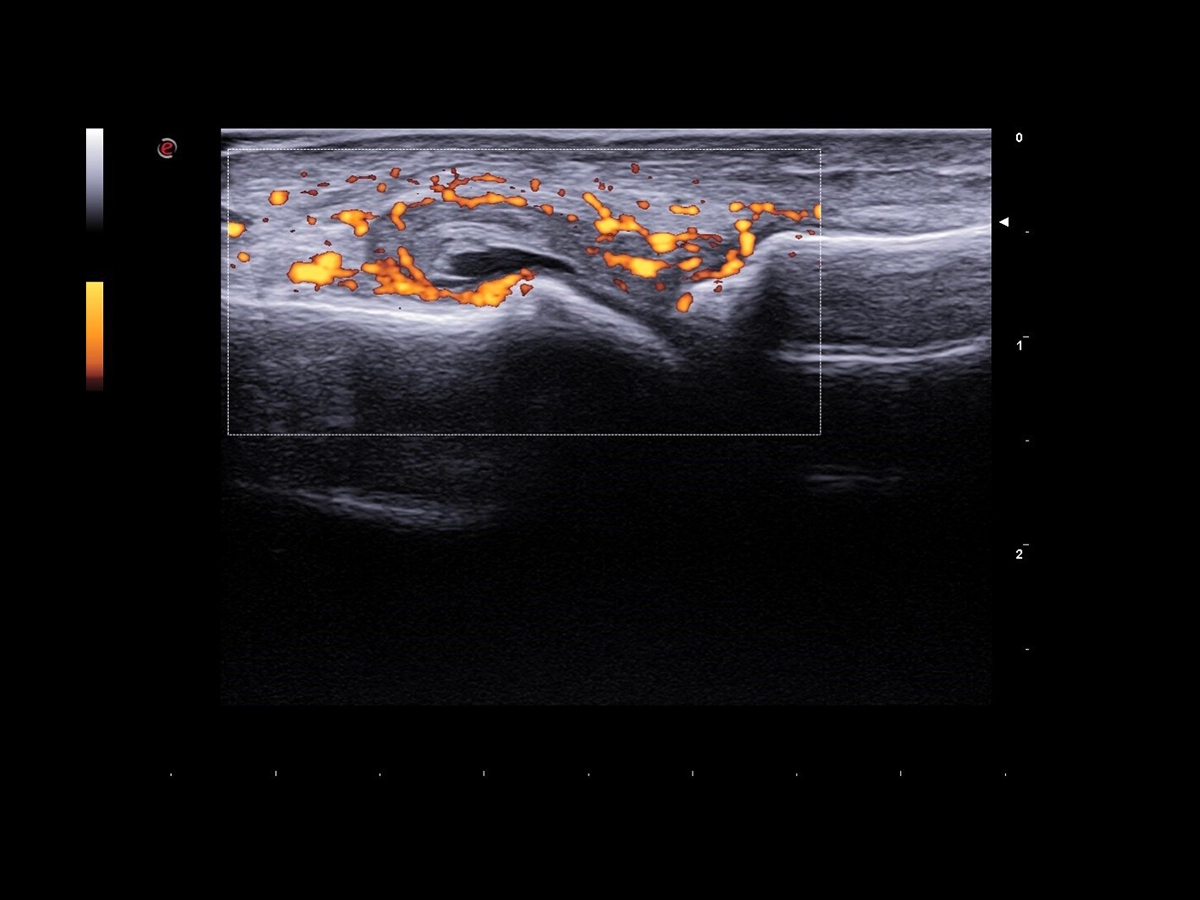

Doppler technology, frequently employed in the assessment of inflammatory conditions, especially in the field of rheumatology, is a non-invasive imaging technique that measures blood flow and can be particularly informative in the context of synovial inflammation.

Esaote Power Doppler, achieving a very high level of sensitivity, and microV, which is a step ahead in the visualization of micro vascularization, deliver high quality Doppler information that the clinician can rely on, while QPack Esaote Technology enables a quantitative assessment of the inflammatory area.